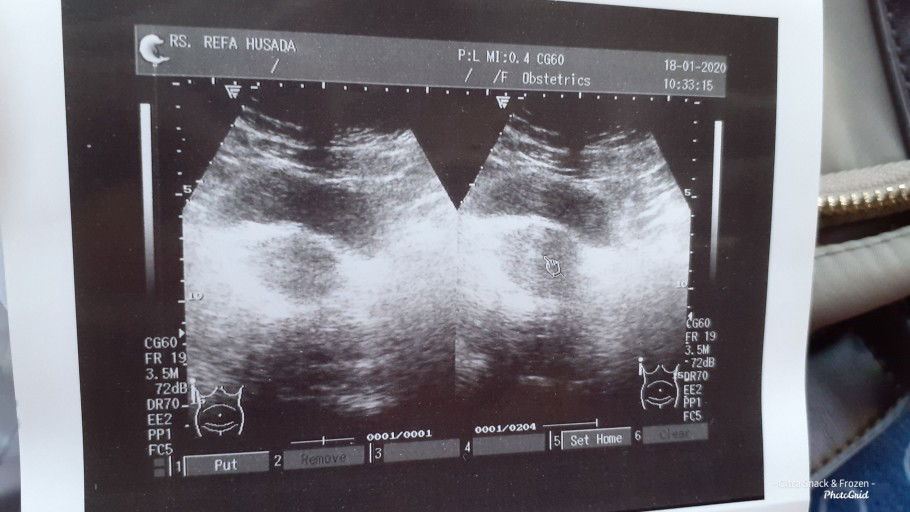

kantung kehamilan lonjong

Bund aku kmrn dh kontrol nih usia 1½bulan khamilan..nah kantong aku bntuknya kyk gt... biasanya kn bulet gt to .. dokter bilang normal² aja cma g puas gt g bsa nnya².. orgnya buru² soalnya antrian bejibun.. Ad g bunda² dsini 6 minggu kantung kehamilan lonjong gt.. sehat² aja babynya smpe gede smpe lairan?? Kta tmnku yg bidan g bulet bukan brti abnormal.. cma aku worry aja.. Gmn bund???

Barusan k dokter nih bund rekomen temen katanya dokternya enak.. coba deh k sana.. emg sih utk usg hasilnya lbh jelas.. 2 hr yg lalu udh tlp dulu nih.. dpt lah no.9.. nah pas dtg ni tadi subhanallah antrinya.. bikin punggungku capek bangt pngen rebahan.. Trs udh 1 jam an lbh nggu.. pas masuk g d tnyain apa2... lgsg usg.. g d jlsin apanya gmn balik kapan .. cma blg tes positif ya.. y mmg hamil.. 1 ½ bulan.. gt doank.. klo aku g blg pernah flek sminggu lalu y g d ksi penguat... suami yg plg kerja capek.. krg tdr.. udh cemberut aja.. dh gt.. obtnya lbh mahal dr dokter pertama aku.. pas tgl tua lagi.. suami syok.. n g nyaman bgt.. pd akhirnya dia memutuskan ntr bln dpn balik lgi k dokter lama aja.. Tp alhamdulillah dokter blgnya sih ni td g butuh pnguat krn ad riwayat flek d kasi lah.. dh gt doank.. y ampun klo kta org jawa g sumbut sma antrinya.. dokternya kurang komunikatif.. mgkin krn pasien yg buanyak bgt... ? tp gpp lah penting sehat smuanya.. btw msih belm kliatan sih babynya.. next balik 4 minggu lagi aja.. Btw.. bunda yg ad riwayat flek.. tp dh berhenti..gmn pengalamannya andai g minum obt penguat gpp ta? Td soalnya nebus obat cma 10 aja.. g d tebus smua.. makasih y bund